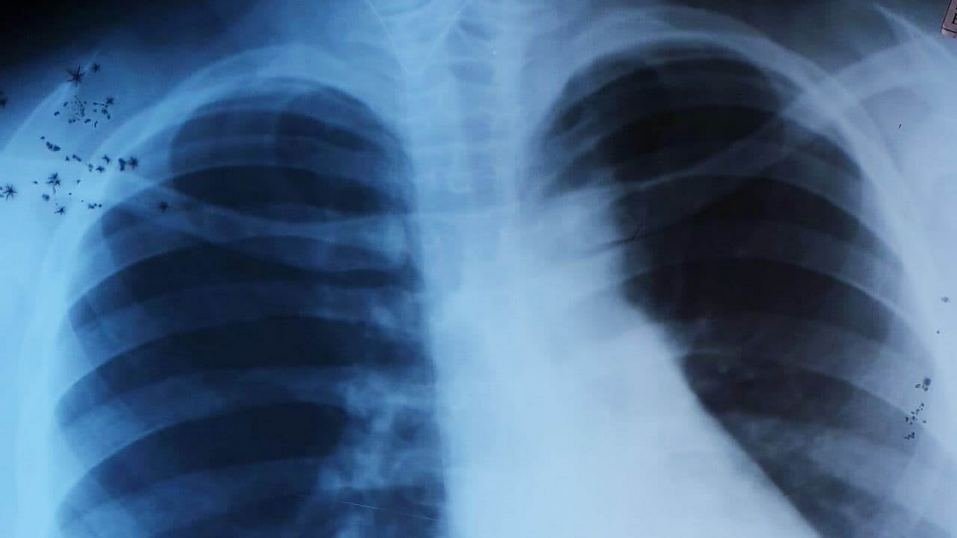

Девочка лечилась по месту жительства, но ничего не помогало. Ее направили в эндоскопический центр для обследования. Доктора заметили у нее проводные хрипы по всей поверхности легких. Они провели бронхоскопию под общим обезболиванием и достали сторонний предмет.